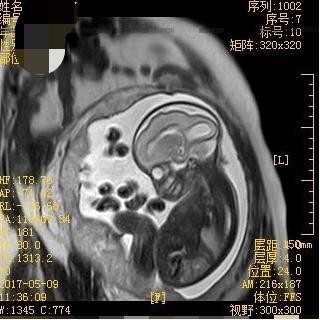

胎儿MRI视野大、软组织分辨率高、不受母体情况如肥胖、子宫肌瘤、羊水过少和多胎等影响,可清晰显示胎儿各个器官信号特点,获得超声不能显示的额外信息,常作为产前超声检查的重要补充手段。近年来,胎儿MRI诊断技术逐渐在临床得到应用并获得重视。胎儿MRI初期主要应用于胎儿神经系统的研究,近年来已经逐渐扩展到胎儿胸部、腹部、盆腔及胎盘等,研究观念从对胎儿单一脏器或系统成像发展为视胎儿为一个整体,这对诊断胎儿多发畸形有重要意义。接下来,我将给大家详细介绍关于胎儿MRI检查的适应症和禁忌症。

中枢神经系统畸形是胎儿MRI最佳适应症,特别是颅后窝畸形,胼胝体发育不良,复杂脑和脊柱畸形,脑室增大原因探查,脑和脊柱肿瘤,脑皮质发育情况评价,神经元移行异常,脑实质缺血或出血,脑、脊髓膨出内容物的鉴别等。

下列情况下,亦可考虑行胎儿MRI检查:超声检查结果不明确者;孕妇过渡肥胖、羊水过少、胎头进入盆腔等不适合超声检查者;胎儿复杂畸形,需要对胎儿进行全面评价者。除MRI检查的一般禁忌症外,胎儿MRI检查无特殊禁忌症。妊娠3个月之前不建议做MRI检查。